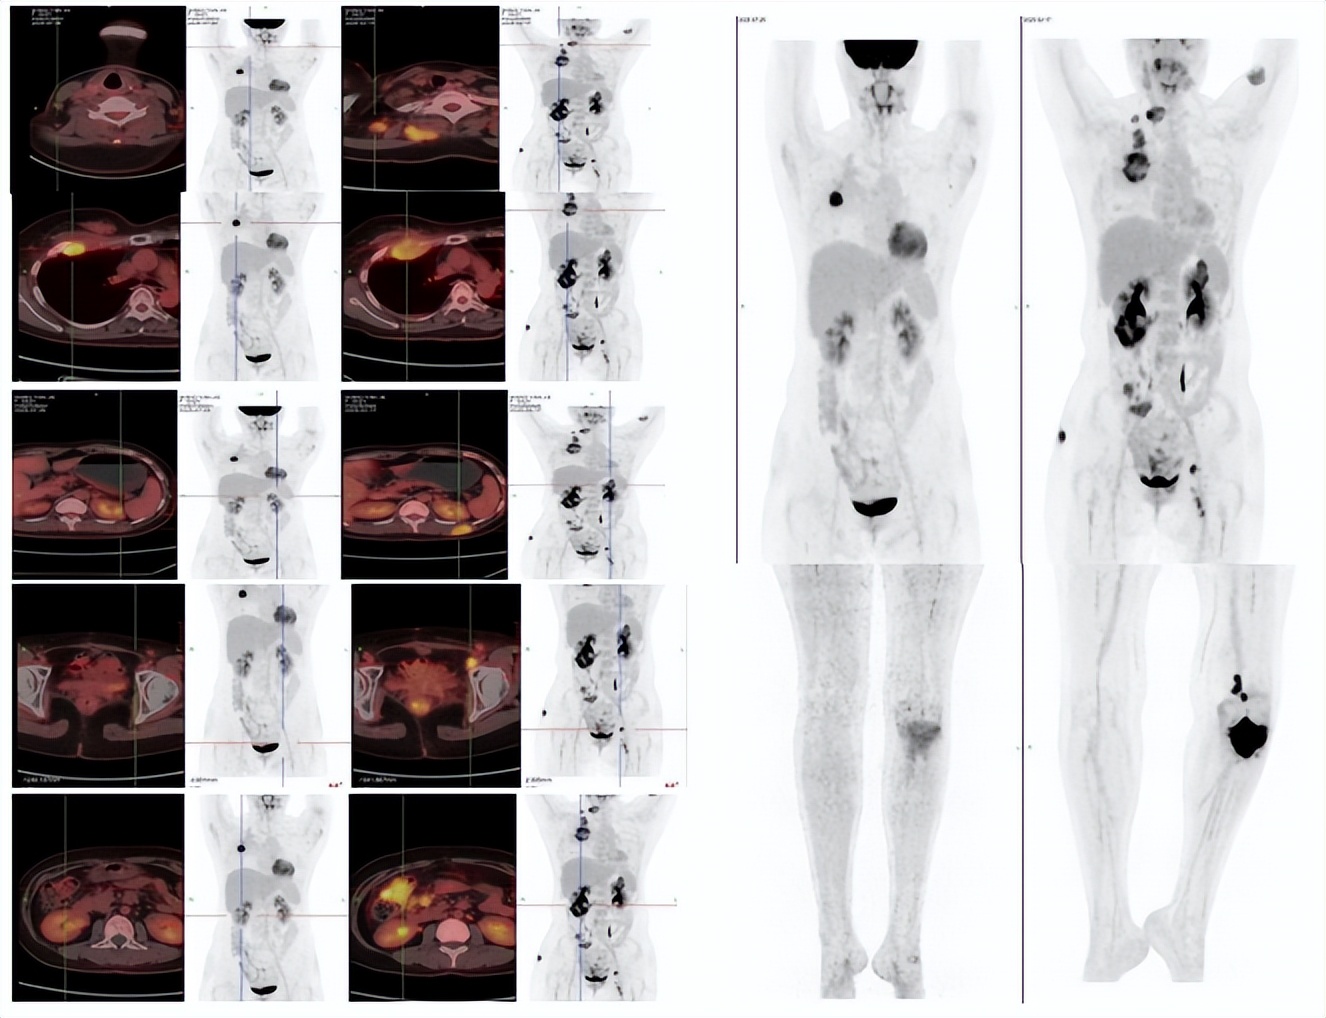

患者经上述治疗两周期后腹部及骨痛症状完全缓解,能独立行走,治疗过程中出现脱发,II度骨髓抑制,未出现其他明显的治疗相关不良反应。2025年07月PET-CT复查评估提示较前显著好转(图2),肿瘤指标降至接近正常水平(图3),总体评价PR,PFS超过6月。

PET-CT:布拉格5月后(2025.07)基线(2025.02)

图2:PET-CT、肉眼可见皮肤转移灶提示较前显著好转